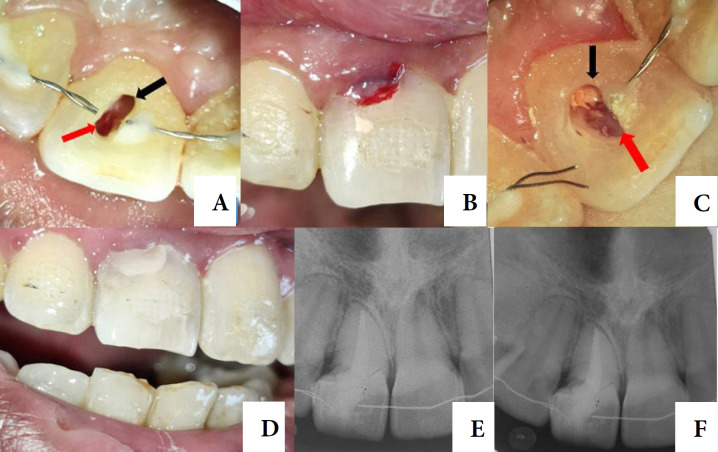

Internal tooth resorption is a subtle proceeding typically occurring in teeth with a history of trauma, chronic pulpal inflammation, or caries-related issues. It is frequently observed in anterior teeth that are more vulnerable and susceptible to injury, but can also affect posterior teeth, often due to pulp involvement in caries. This case report illustrates the handling of a resorption in the cervical third of the root. A 28-year-old female patient was referred for endodontic and esthetic treatment for her primary complaint of pink spot staining in her upper left central incisor's crown. The tooth had symptomatic apical periodontitis. Final Diagnosis was Class 4 invasive cervical resorption. This case study outlines the effective management of an extensive internal root resorption using a non-surgical approach and the application of MTA as repairing material with thermo-plascticized gutta-percha as an obturation material. The treatment resulted in the resolution of symptoms and the restoration of periapical tissues. Timely detection, addressing the underlying cause, and effective care of the invasive cervical resorption are essential for achieving a favorable treatment outcome. Obtaining positive results required a patient-centered approach, well-planned therapy, and an accurate diagnosis.